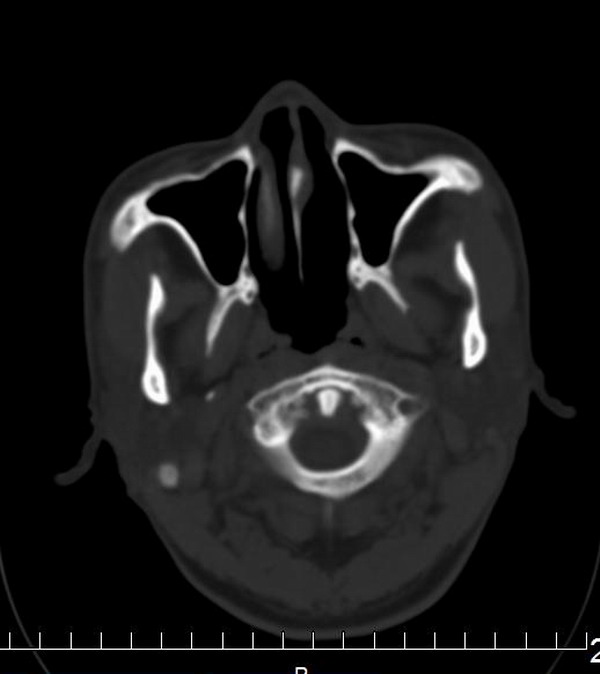

男,56y,自觉左上颌部不适,有时可闻及腥臭鼻涕味。

额骨右份不规则增厚,密度增高,内可见低密度影。

诊断:骨纤维异常增殖症。

纠正:额骨左份不规则增厚。

支持左额骨水平部、蝶骨大翼、颧骨骨纤。